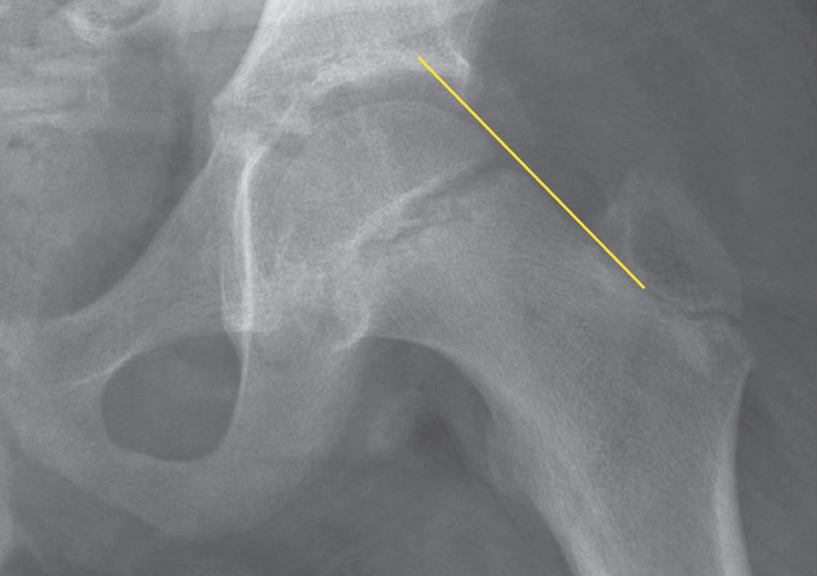

The radiographs show widening of the proximal femoral growth plate. A line drawn along the superior edge of the femoral neck (the Klein line) normally crosses the epiphysis. In our patient’s radiograph, however, the epiphysis falls below this line (Figure).

Figure – A radiograph of our patient’s hip shows that the femoral epiphysis lies below the Klein line.